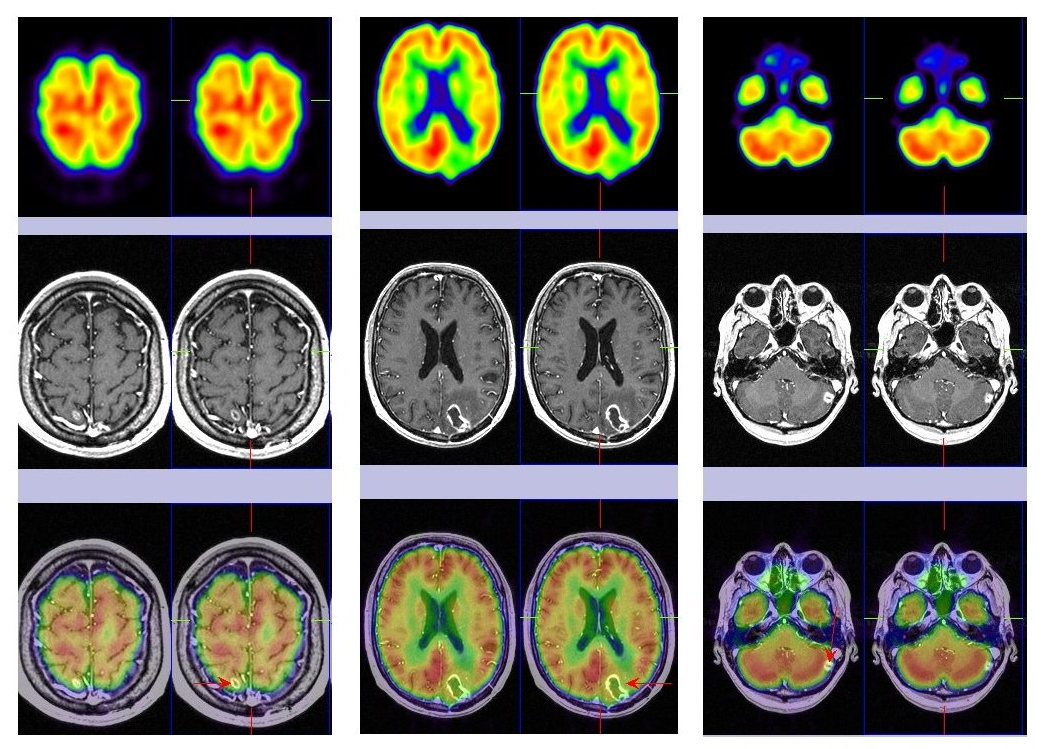

La paciente muestra una franca mejoría neurológica y al cabo de 5 meses se le realiza como estudios de re-estadificación un PET-TC corporal que fue normal y una PET-RM cerebral que muestra ausencia de captación de 18F-FDG en las tres lesiones cerebrales conocidas (fig. 1), siendo el hallazgo indicativo de cambios postratamiento (radionecrosis). La paciente recibe corticoides a dosis decrecientes, con buena respuesta clínica.